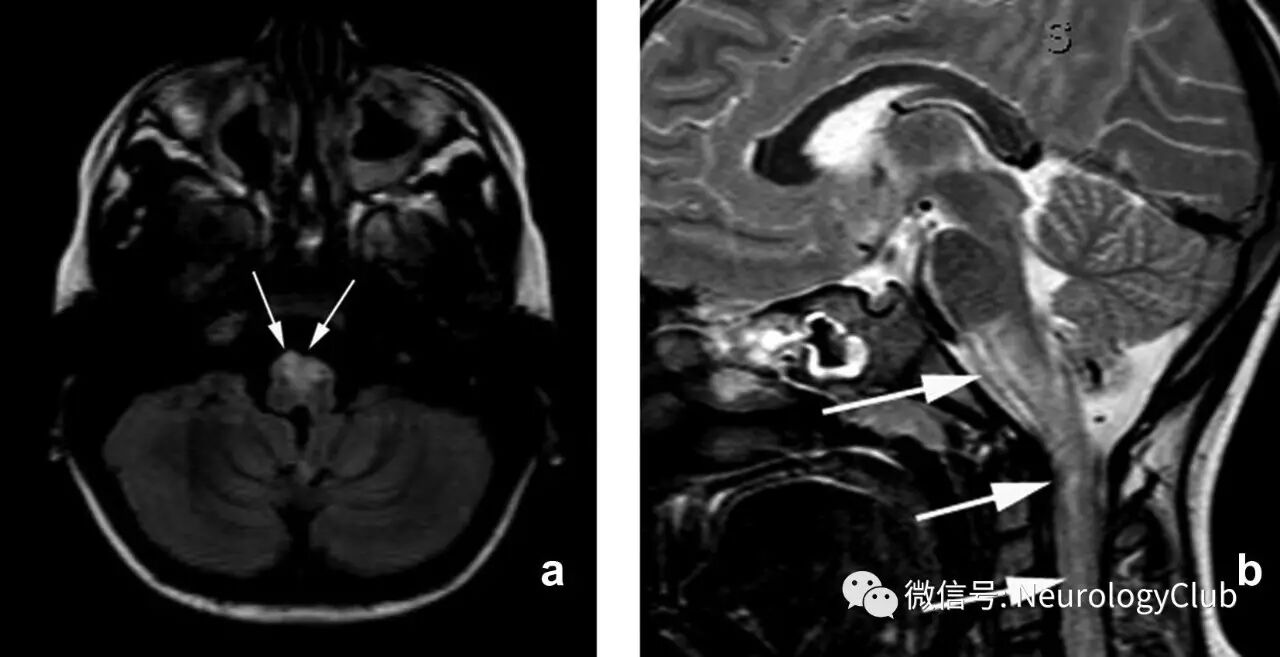

案例3:42岁男性,既往体健,因枕部头痛、恶心、呕吐和失衡入院。血压:190/110mmHg。神经科查体示腱反射亢进,失调步态,双侧轻度辨距不良。入院化验示肌酐9.68mg/dl,尿素氮194.7mg/dl,余无殊。诊断为终末期肾病,予血液透析治疗。2周后临床症状好转。

(图12:起病时MRI表现

(图13:复查时的MRI表现)